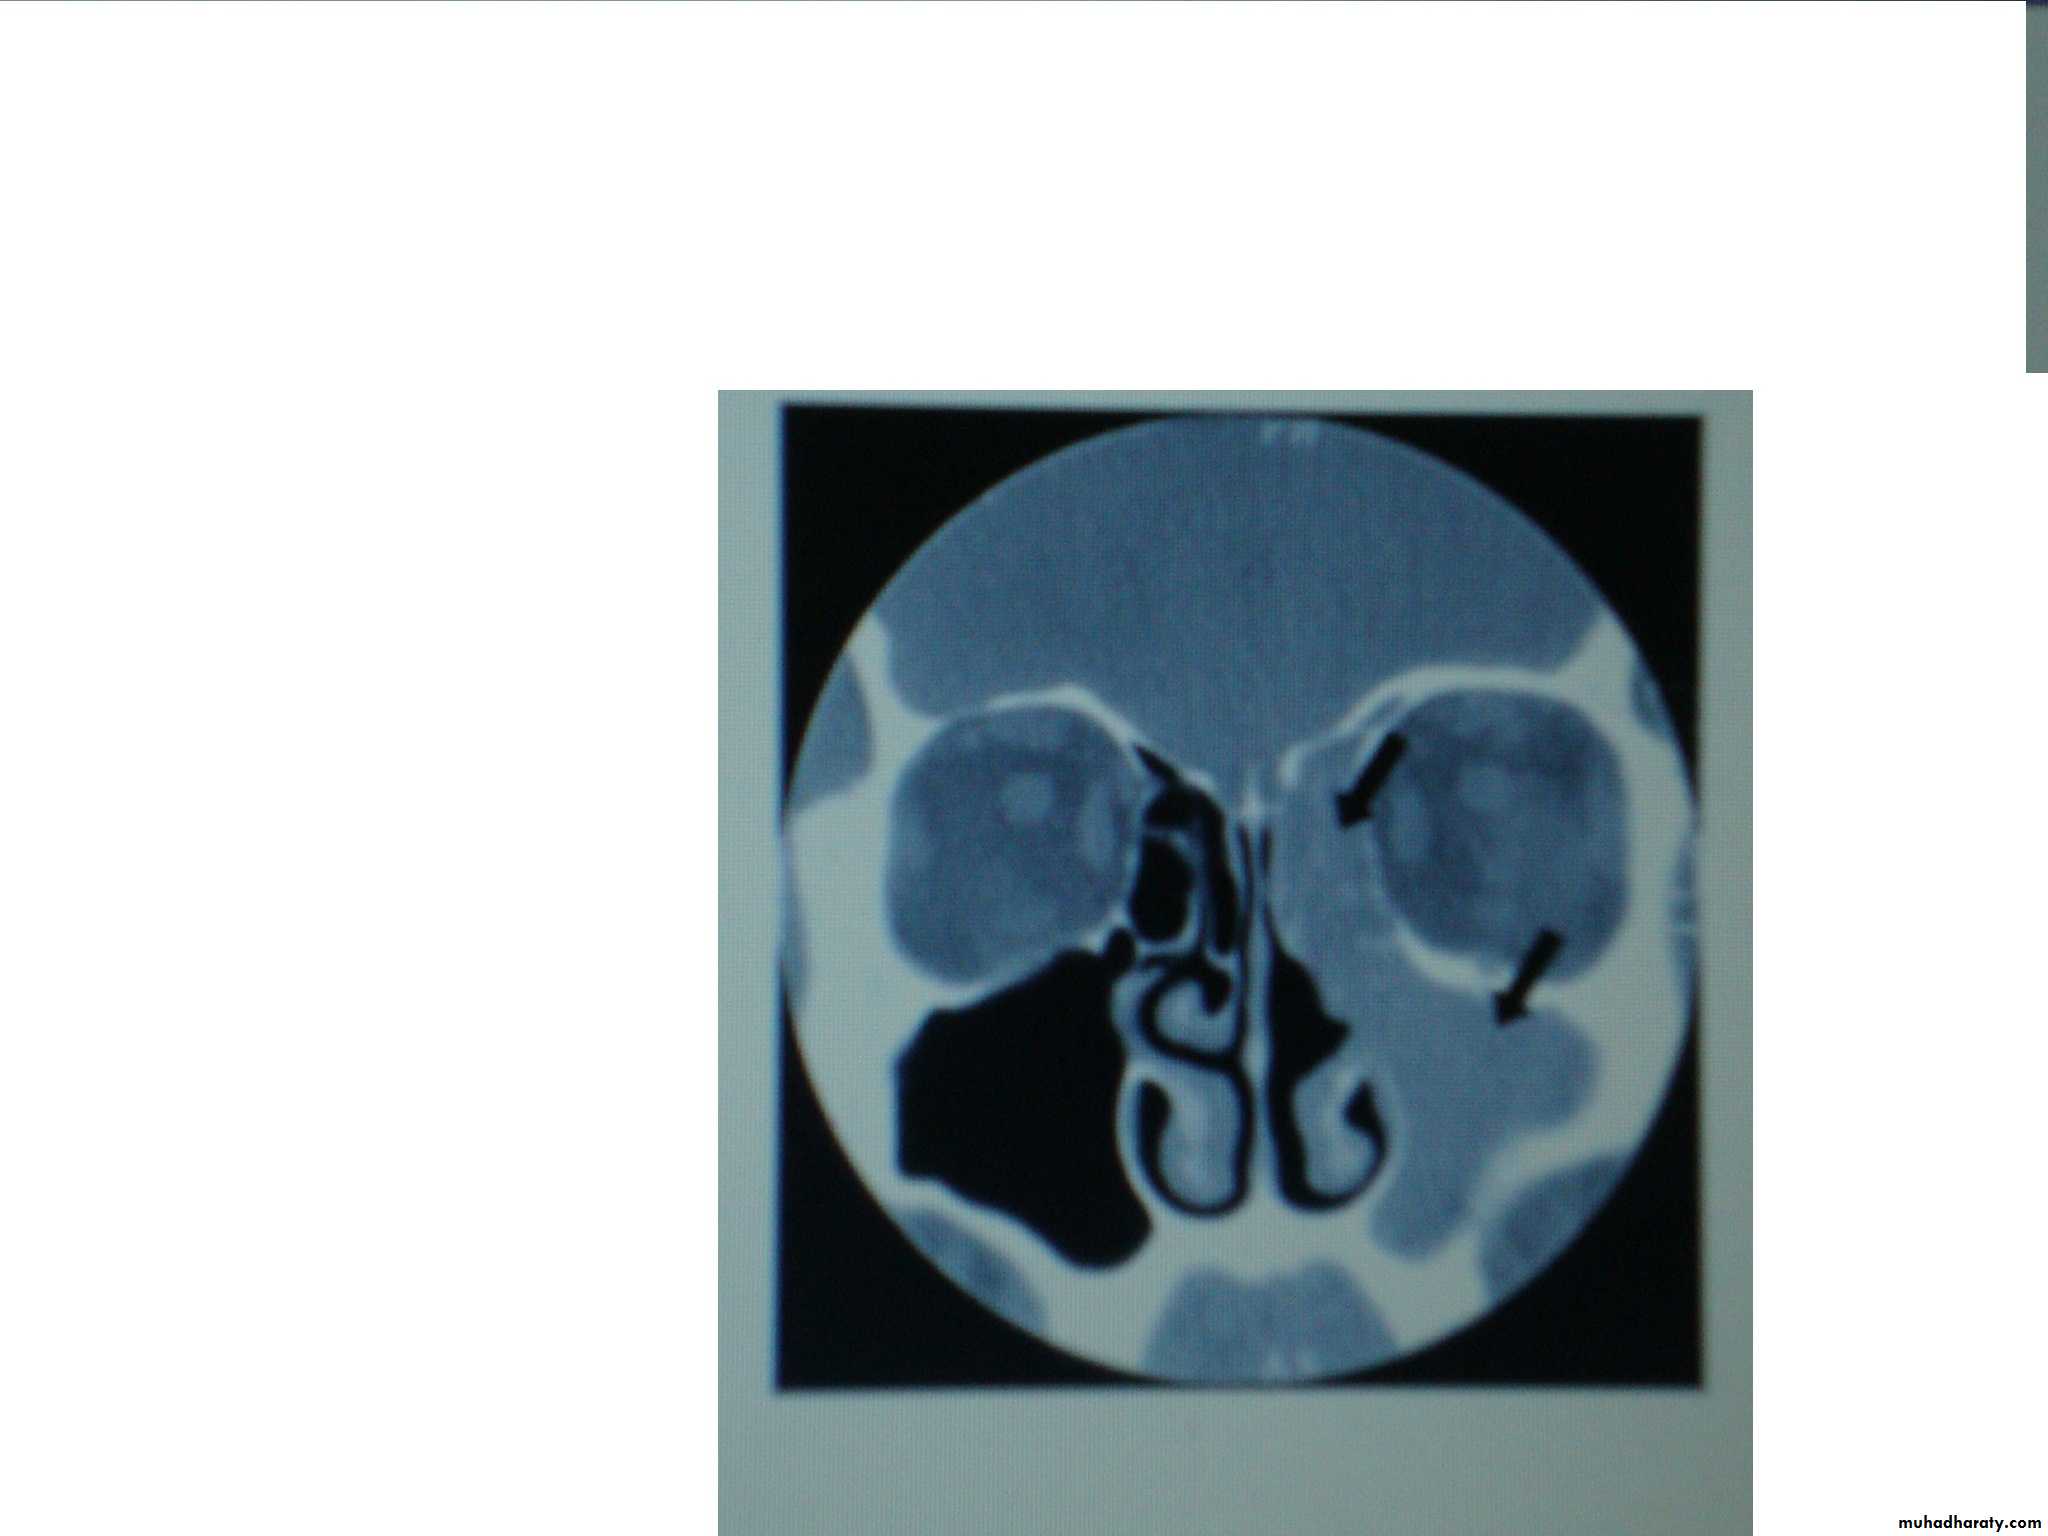

Plain X-ray (occiptomental view) may show:

Sinus mucosal thickening.

Fluid level

Total opacification of the sinus.

CT scan.